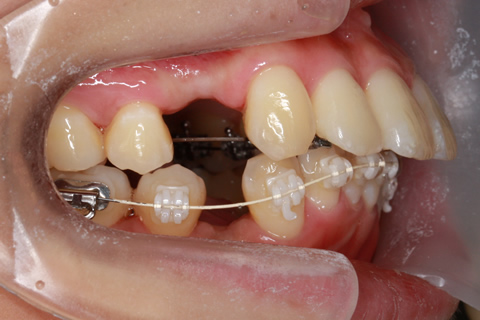

治療中(開始直後)

治療中(開始半年後)